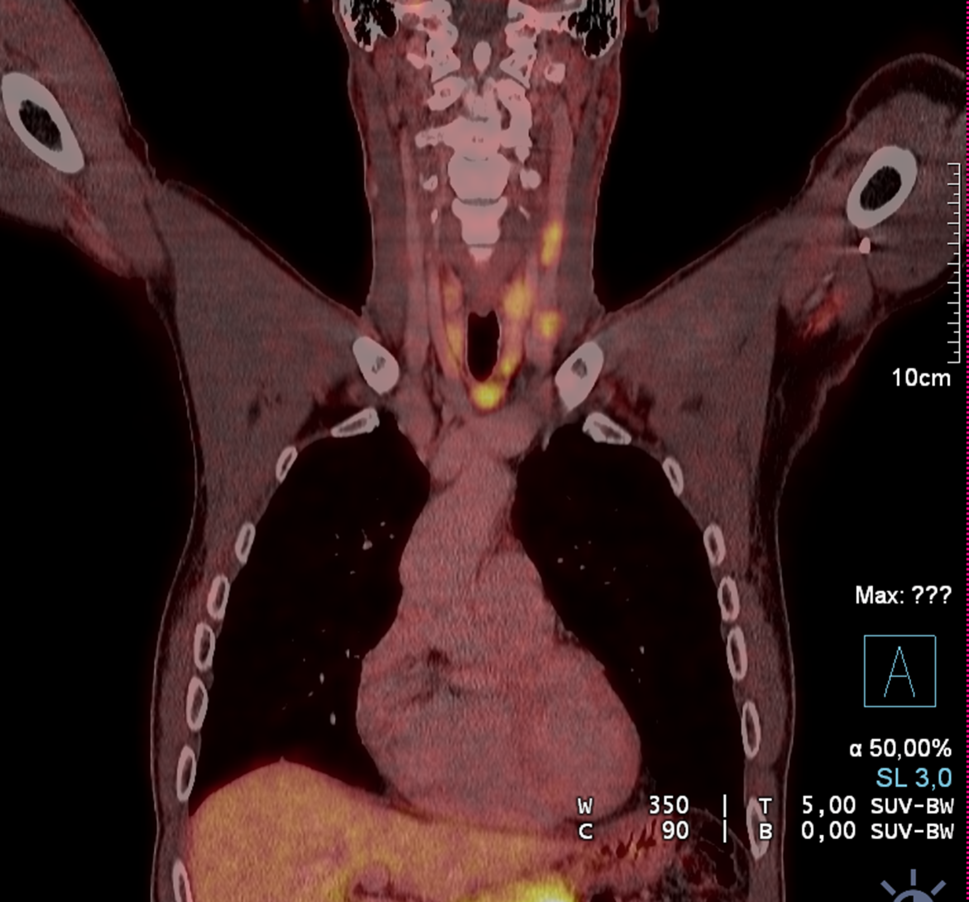

Abb. 2

a I123 Szintigraphie mit mediastinalem Fenster – einer intrathorakalen Struma entsprechend mit morphologischem CT Korrelat einer riesigen Struma (1) mit isoliert intrathorakalem Anteil (2) bei derselben Patientin (b)

Auch obliegt es letztlich dem Chirurgen, die Ausdehnung einer Struma bereits präoperativ möglichst gut abzuklären. Bei Ausdehnung einer Schilddrüse in den Substernalraum bzw. fehlender sonographischer Abgrenzbarkeit nach caudal ist ergänzend ein Schnittbildverfahren zu wählen, das eine intrathorakale Ausbreitung oder auch isoliert intrathorakale Anteile erfasst und erkennen lässt, ob das vordere oder das hintere Mediastinum betroffen ist. Diese Information ist ganz wesentlich für die Operationsstrategie und die Frage, ob eine Erweiterung des Zugangsweges (z. B. Sternotomie) notwendig sein könnte. Die Szintigraphie kann hier erste Hinweise liefern, wenn das diagnostische Fenster in das obere Mediastinum erweitert wird (Abb. 2a). Als weiterführende Diagnostik ist ein CT ohne Kontrastmittel oft ausreichend (Abb. 2b). Jodhältige Kontrastmittel sind präoperativ grundsätzlich zu vermeiden, da im Falle von differenzierten Karzinomen verbliebene Schilddrüsen- oder Tumorzellen jodgesättigt sind und eine Radiojodtherapie dadurch nur verzögert möglich ist. Ein MRT kann speziell bei zystischen papillären Tumoren das Ausmaß einer Metastasierung in der T2-Gewichtung eindrucksvoll zeigen (Abb. 3) und ist darüber hinaus bei Verdacht einer Infiltration des Aerodigestivtraktes sehr zu empfehlen.